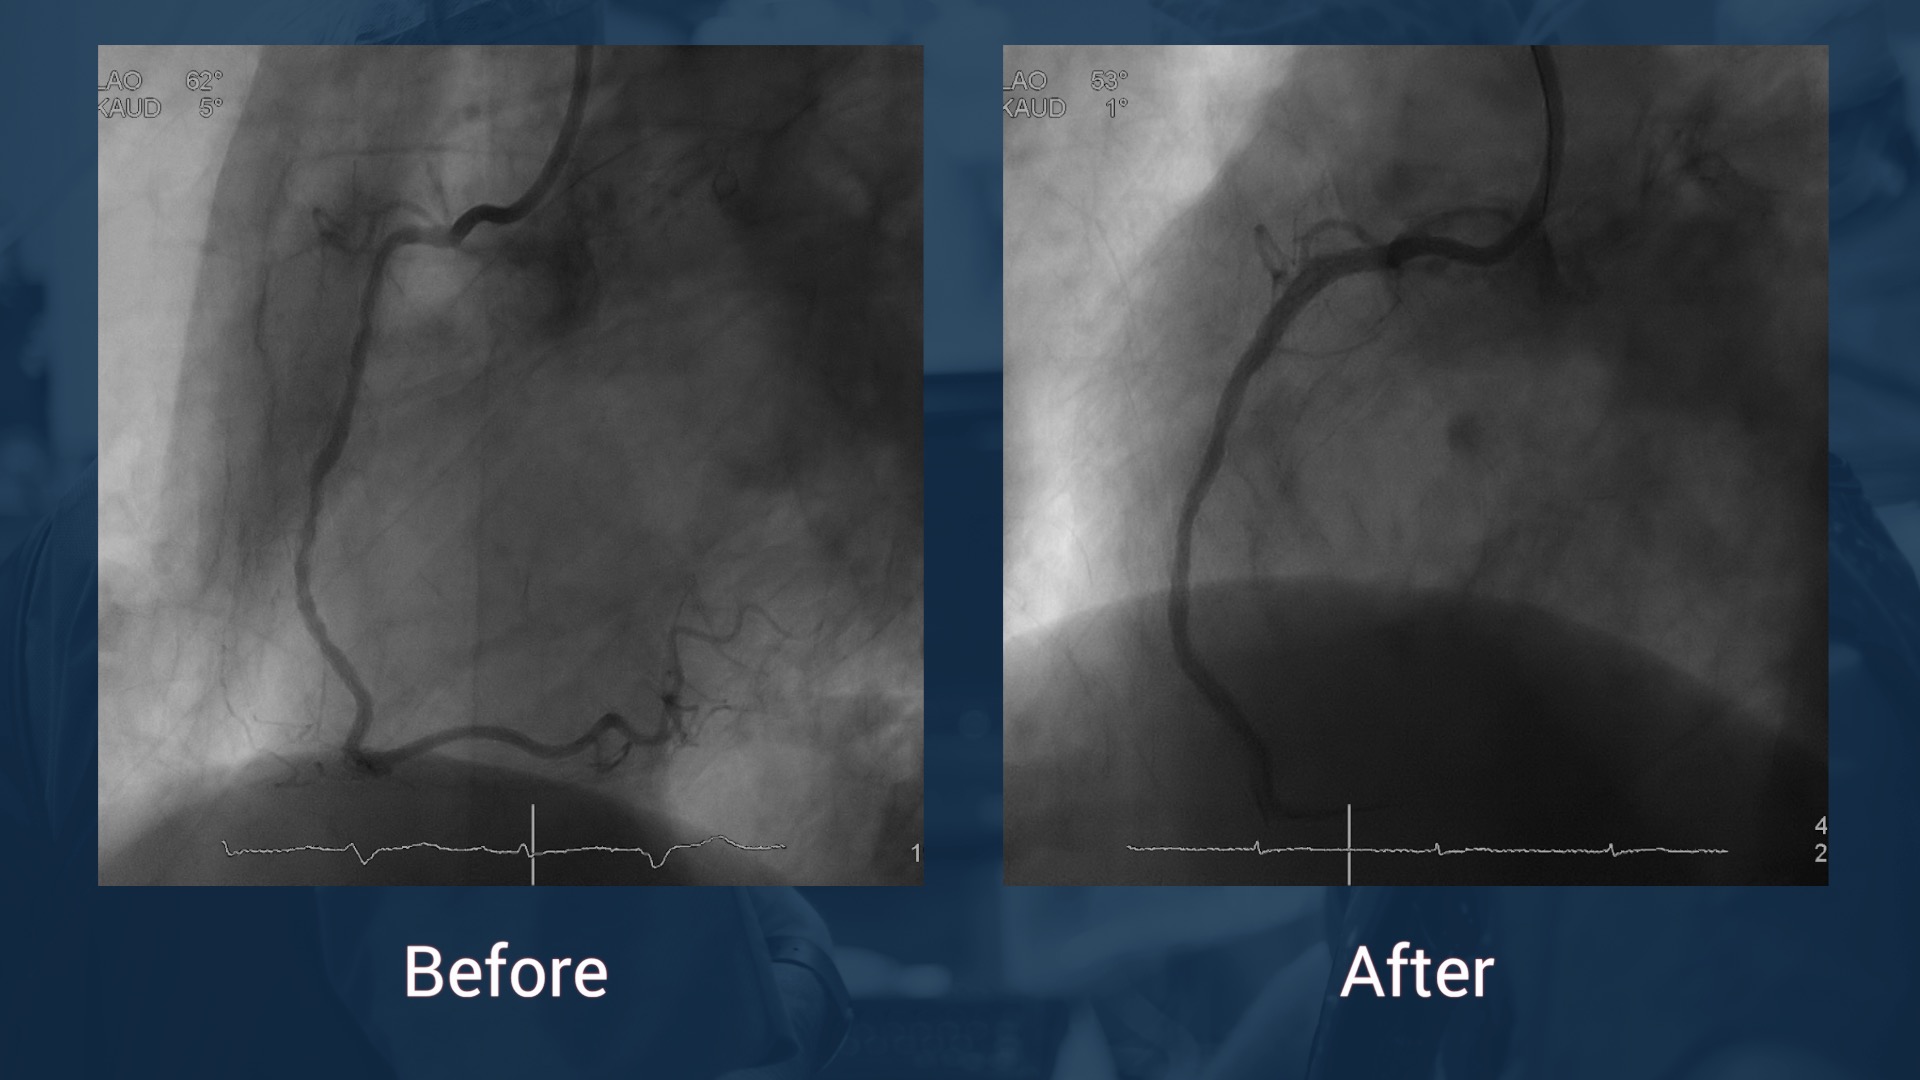

CAG 14.7.17: LAD without stenosis, CX without stenosis, in-stent reocclusion of the RCA

J-CTO score: 1